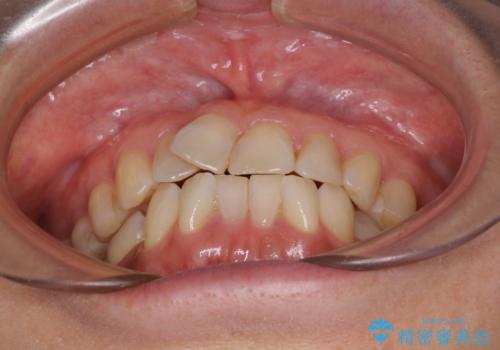

- 前歯のデコボコを気にして来院された患者様です。

インビザラインでもワイヤー装置でも対応可能であったので、両者のデメリットをご説明し、選択していただくことになりました。

マウスピース矯正の装着時間の長さや自己管理の重要性を煩わしいと感じられ、低依存で確実に治療ができるワイヤー矯正を選択されました。

舌突出癖により、上下前歯がなかなか接触せずに治療期間を要しましたが、舌のトレーニングにより無事に治療を終えることができました。